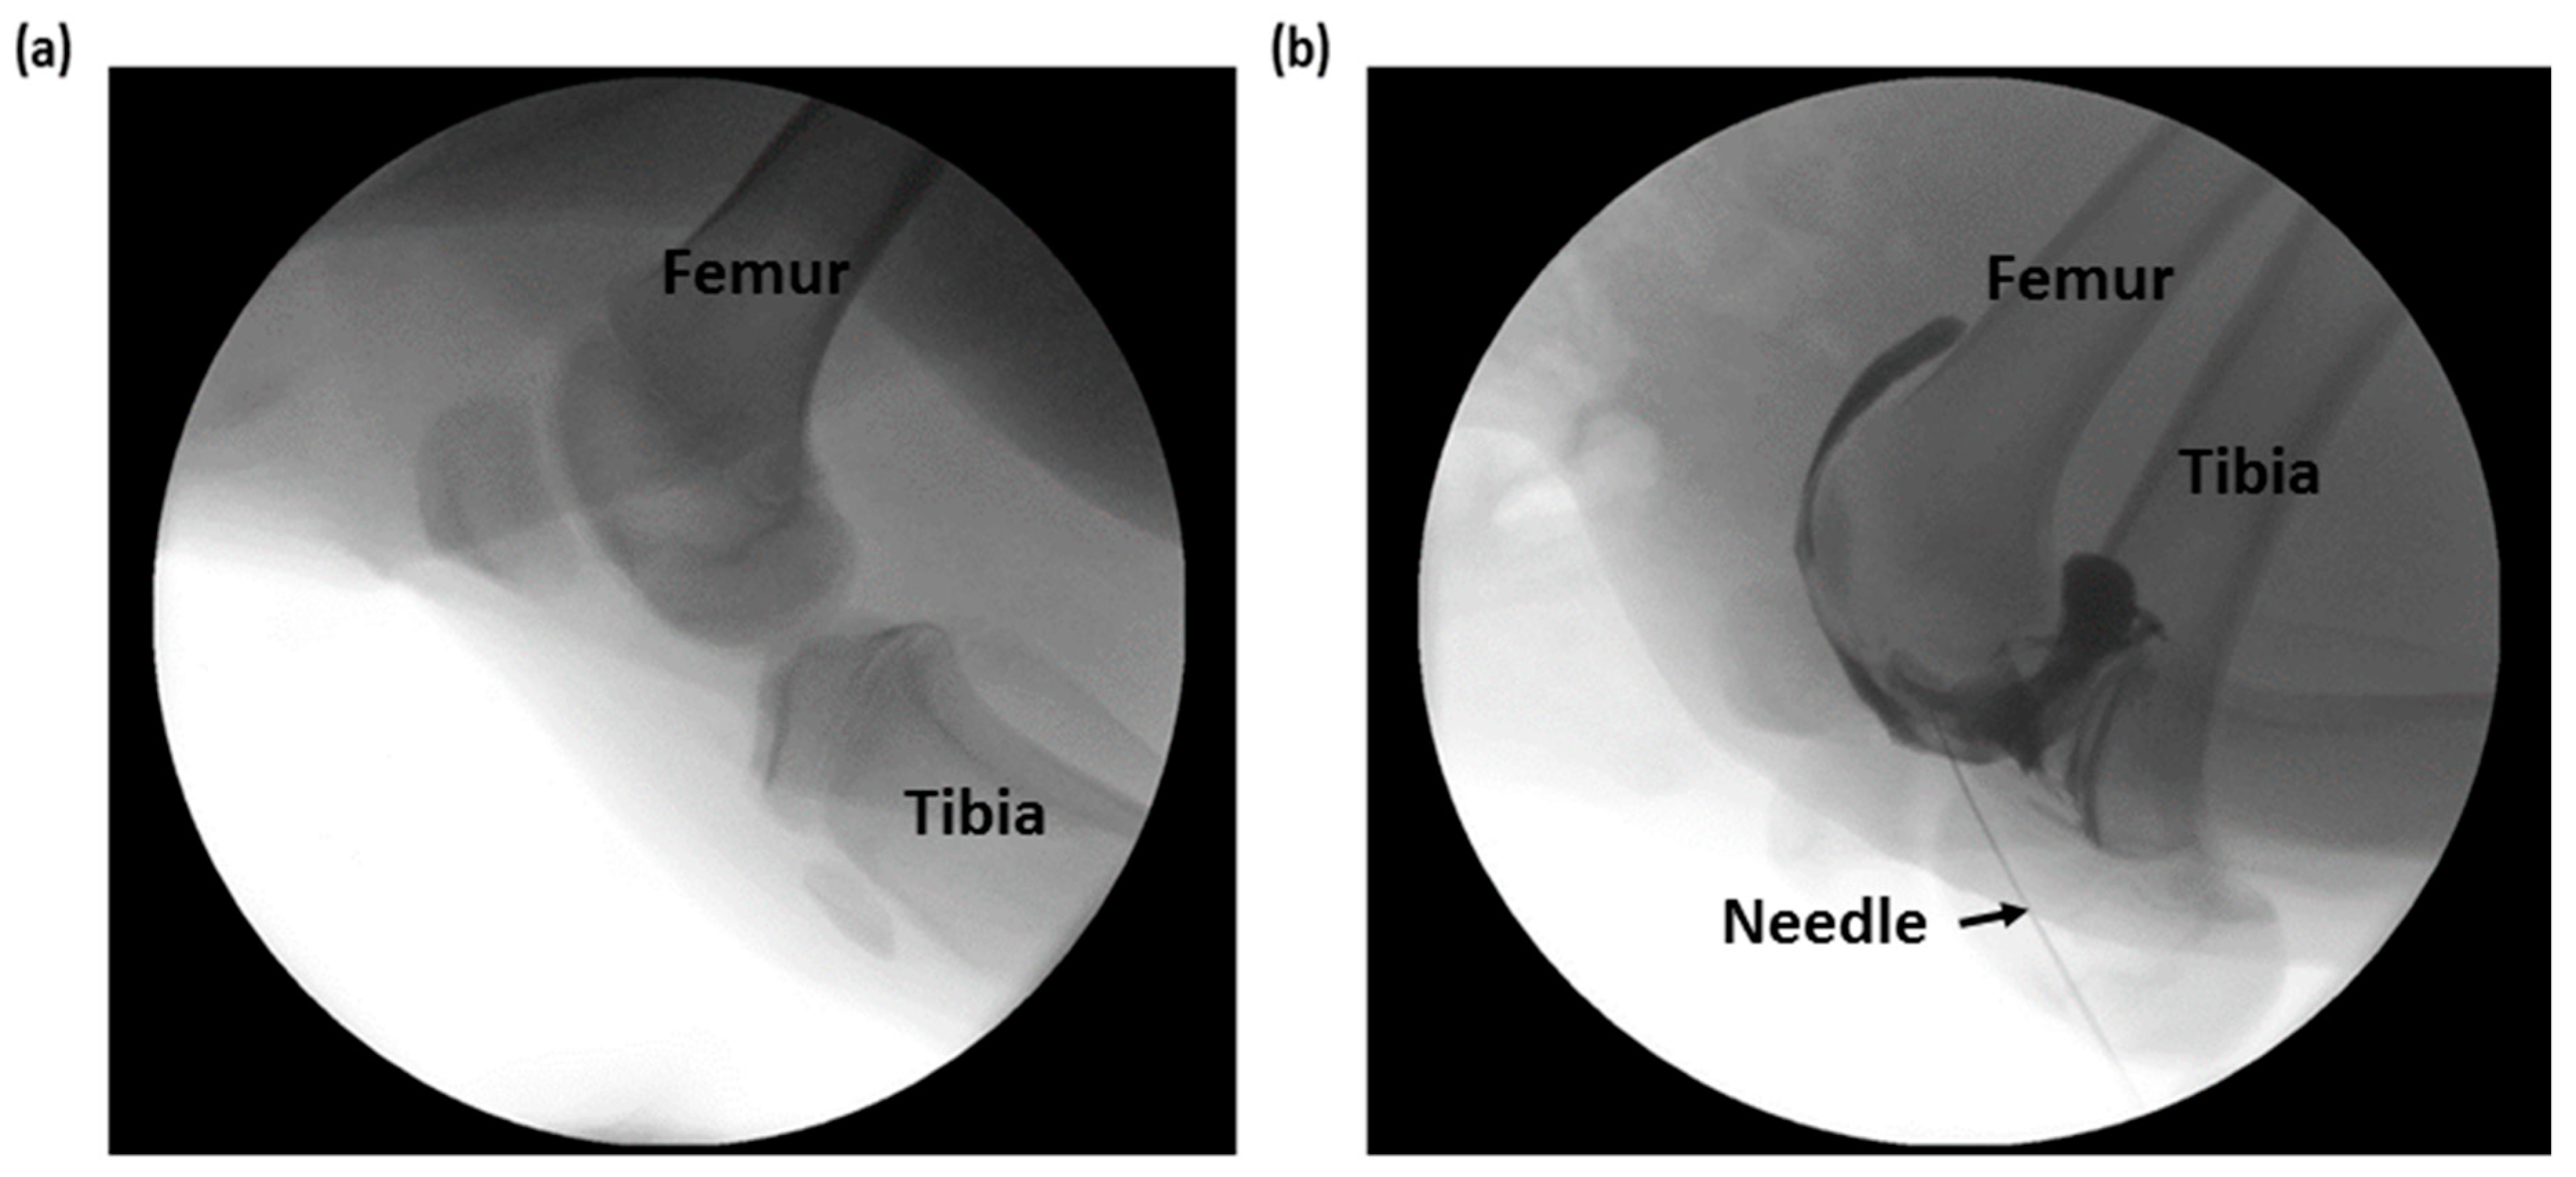

2.2. Experimental Setup